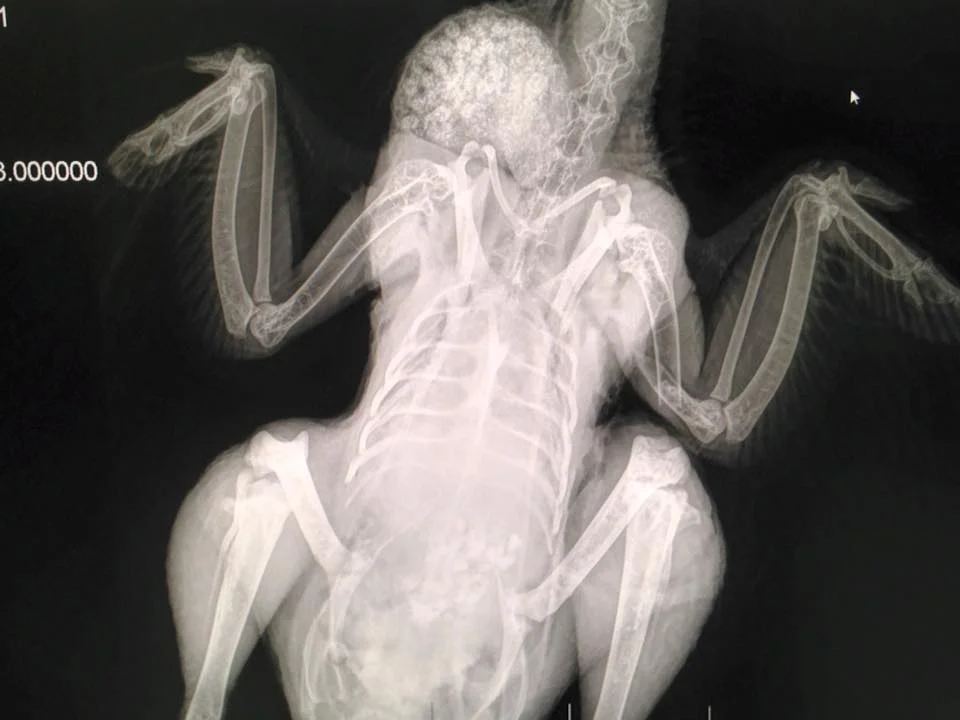

X-ray of a chicken with a broken wing. The chicken required sutures and a splint and recovered wonderfully.